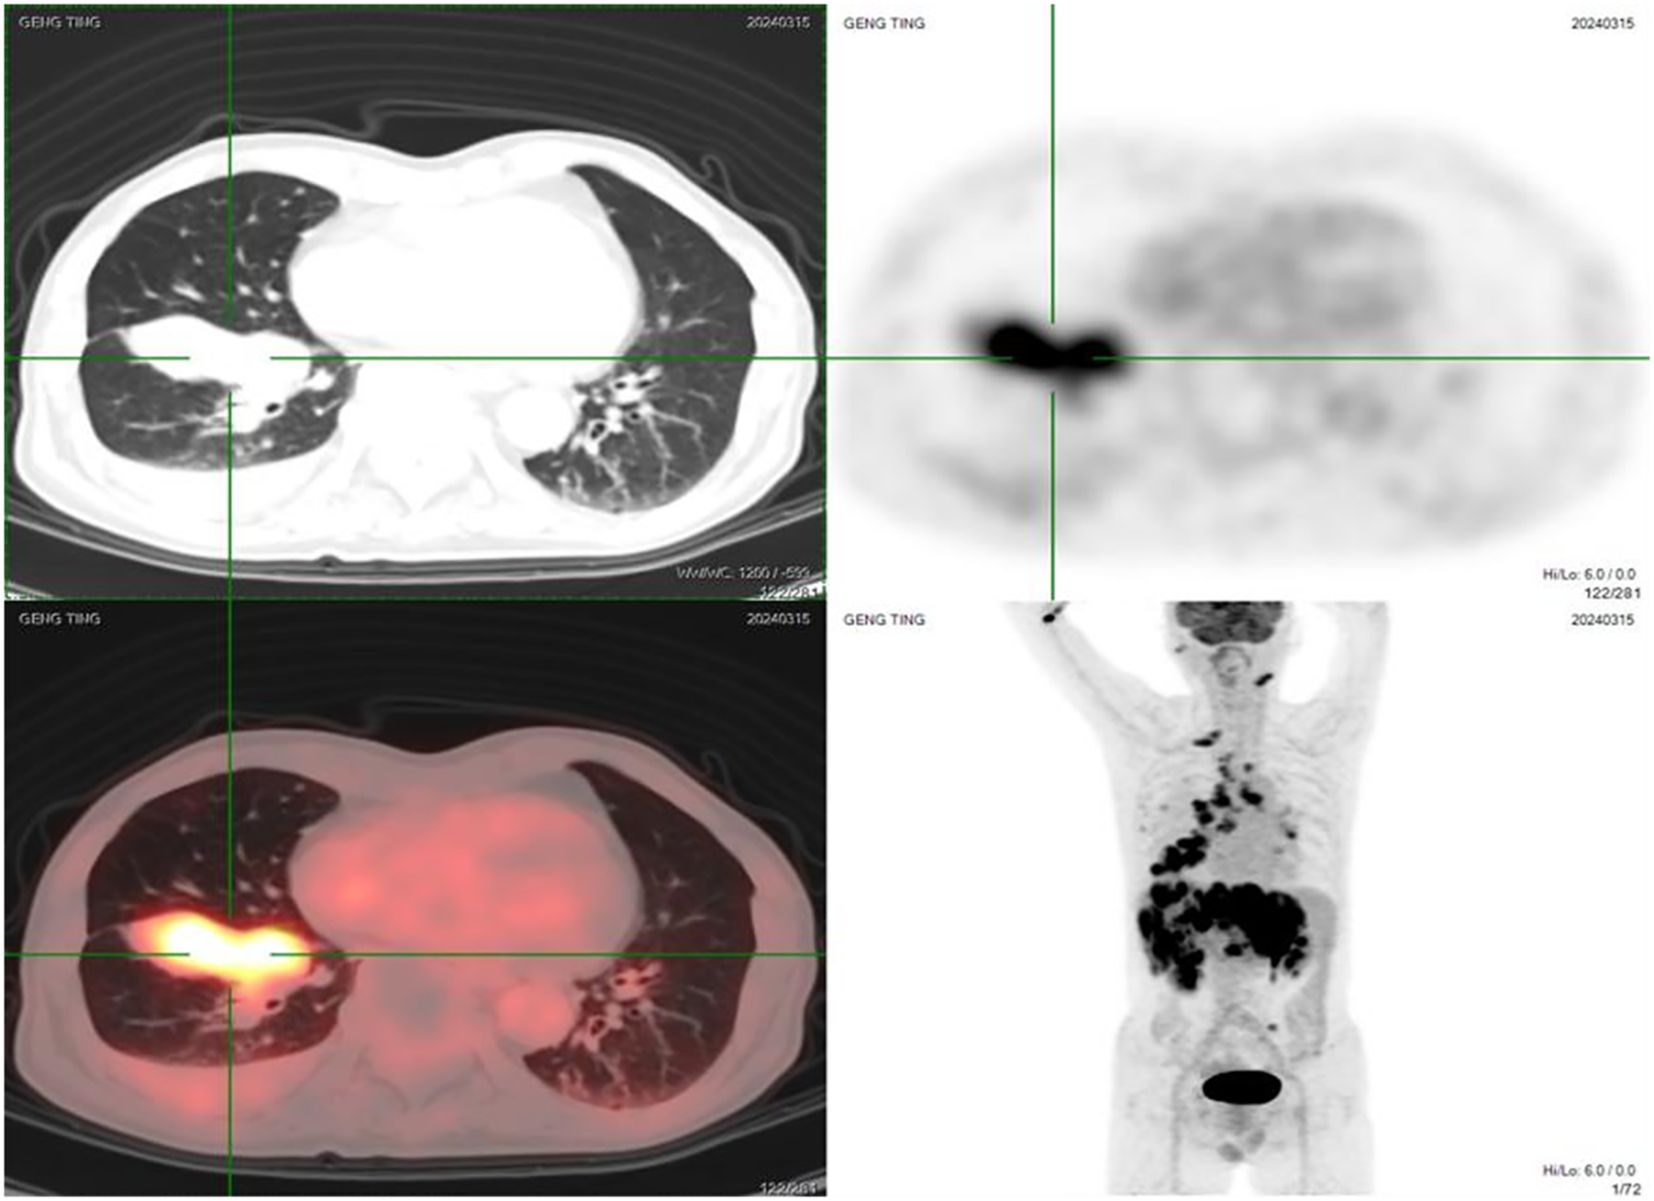

On March 13, 2024, a biopsy of a lesion in the right lower lobe was performed. Pathology suggested pulmonary neuroendocrine carcinoma. Positron Emission Tomography/Computed Tomography (PET/CT) on March 15, 2024, revealed:

1. A soft tissue density mass near the hilum in the anteromedial basal segment of the right lower lobe (with corresponding segmental bronchial occlusion), demonstrating increased fluorodeoxyglucose (FDG) uptake, suggestive of central lung cancer.

2. Multiple bilateral pulmonary metastases, with right pulmonary lymphangitis carcinomatosa.

3. Metastatic lymphadenopathy in the right pre-parotid region, left submandibular region (level IB), right supraclavicular fossa (level IV), bilateral hilar regions (10R/L), mediastinum (2R/L, 4R/L, 7), and left mesenteric region.

4. Multiple intracranial metastases.

5. Multiple hepatic metastases.

6. Multiple osseous metastases involving the right sternal end of the clavicle, L2 vertebral body, left sacral ala, left ilium, and right pubis (Figure 1).

Figure 1. Pre-treatment PET/CT images (March 15, 2024) showing the primary lesion in the right lower lobe, multiple bilateral pulmonary metastases, extensive lymph node metastases, brain metastases, liver metastases, and bone metastases.